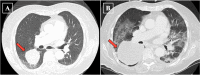

It is well-documented that lung and bronchus cancers are the leading cause of cancer death in the United States in both male and female patients, with lung adenocarcinoma accounting for the highest prevalence of lung cancers. Significant eosinophilia in the setting of lung adenocarcinoma has been documented in a few reports, being described as a rare paraneoplastic syndrome. We report on an 81-year-old female with hypereosinophilia-associated lung adenocarcinoma. A chest film showed a right lung mass, which was not apparent on a chest film 1 year prior, in the setting of significant leukocytosis of 27.90 x 103/mm3 with eosinophilia of 6.40 x 103/mm3. A computed tomography (CT) chest, obtained during admission, demonstrated significant right lower lobe mass enlargement since the previous study completed 5 months prior, with new occlusion of bronchi and pulmonary vessels to the region of the mass. Our observations are consistent with prior reports showing that the presence of eosinophilia in lung cancers may indicate rapid disease progression.